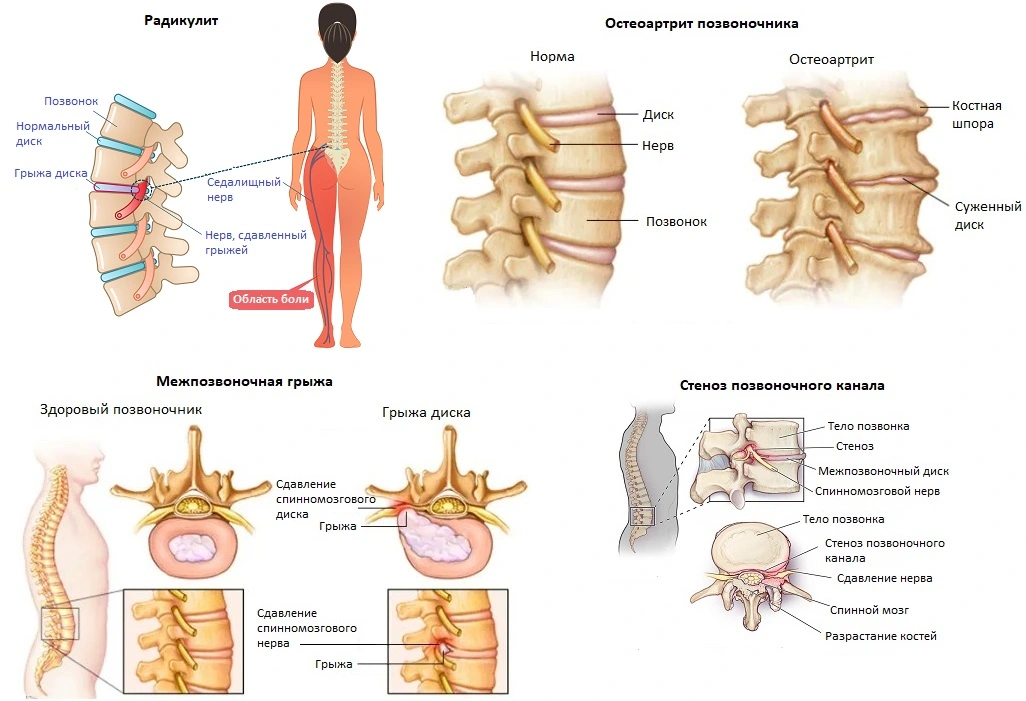

Структура позвоночника: сегменты и тазовые отделы в фотографиях